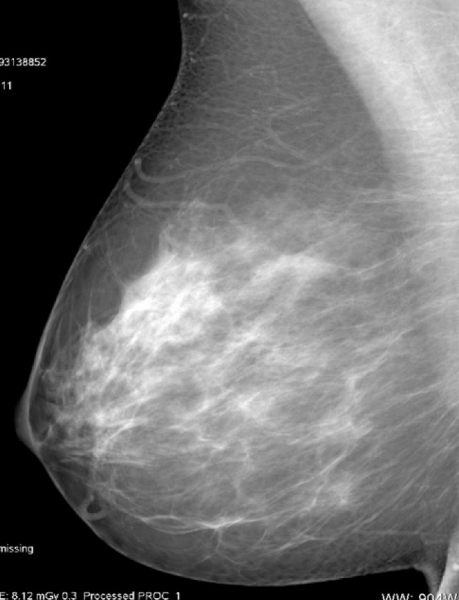

Fatty breast tissue.